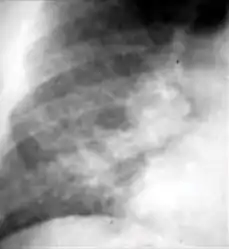

3. Nodule with poorly defined margins - Round density within the lung parenchyma, also called a tuberculoma. Nodules included in this category are those with margins that are indistinct or poorly defined (tree-in-bud sign[3]). The surrounding haziness can be either subtle or readily apparent and suggests coexisting airspace consolidation.

Chest x-ray showing nodule with margins that are indistinct or poorly defined (tree-in-bud sign) in post-primary pulmonary TB.